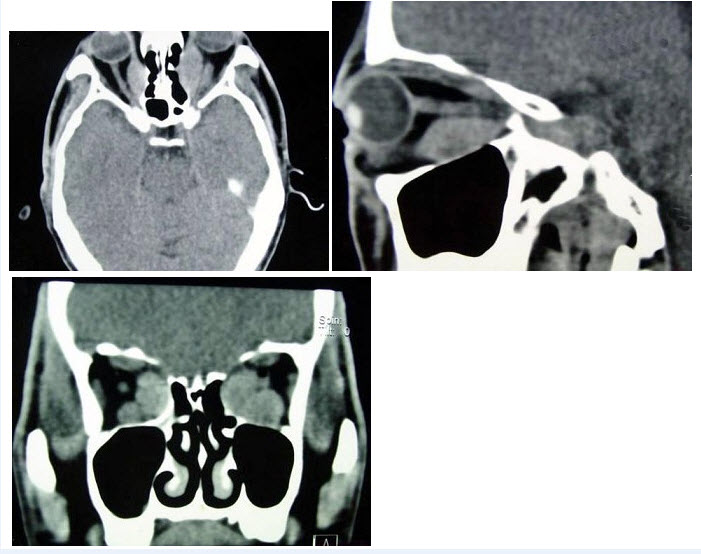

56、单项选择题

男孩,2岁,双眼疼痛1年,右侧眼球突出。CT平扫如图:

A.脉络膜

B.睫状体

C.虹膜

D.视网膜

E.玻璃体